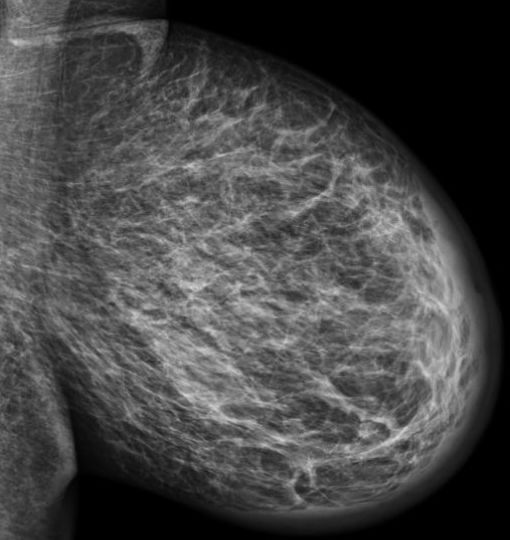

| Beispiele | invasives duktales Karzinom | klassische Trias: Kernschatten, strahlige Ausläufer, Mikrokalk![]() |